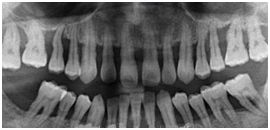

患者女性,59岁,右侧后牙咀嚼无力,刷牙时牙龈出血。无系统性疾病。口腔检查显示全口多数牙牙石(++),牙龈红肿,探诊出血,牙周袋袋深4——6mm,右下后牙有Ⅰ——Ⅱ度松动,X线片如图所示: